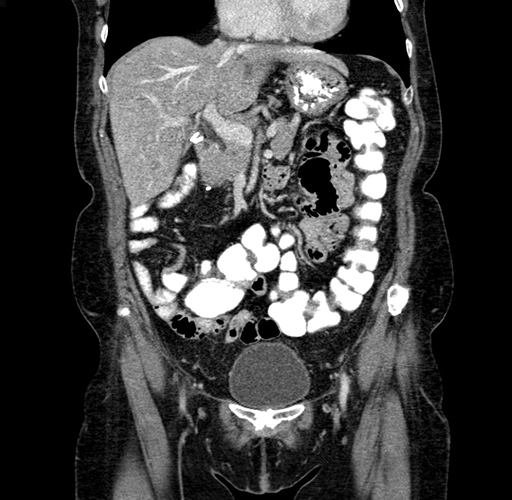

Coronal Venous